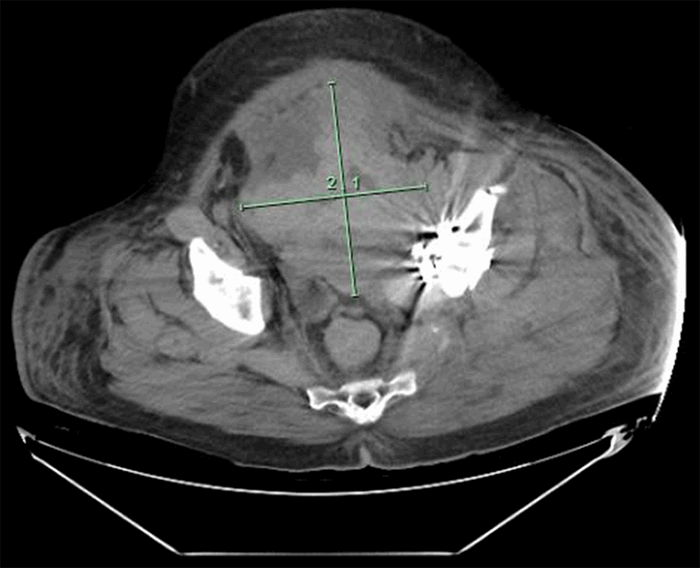

A noncontrast computed tomography (CT) scan was obtained to investigate the etiology of the hemorrhage. This revealed a new RPH with a decompressed bladder and bilateral hydronephrosis (Figure 2). Additional studies confirmed that the AKI was due to obstructive uropathy due to the RPH. Therefore, he returned to the operating room for evacuation of the RPH and exploration for a vascular source of the hemorrhage. Approximately 650cc of hematoma was evacuated. Bleeding from a perivesical arterial branch was controlled with hemoclips.

Figure 2. Axial CT Images Obtained on Hospital Day 12 Demonstrating Pelvic Hematoma Measuring 14.33 cm × 12.40 cm. Published with Permission